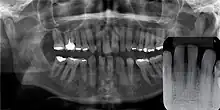

Gingival cyst of adult is a rare condition. The incidence is less than 0.5%. It is formed from the rests of dental lamina.[11] It is found in the soft tissues on the buccal and labial portions of the jaw. It usually occurs on the facial gingiva as a single small flesh colored swelling, sometimes with a bluish hue due to the cystic fluid. Sometimes, it may occur in cluster, either unilaterally or bilaterally or on the lingual surface of the alveolar process. It is most commonly seen in the canine and premolar regions of the mandible, and are sometimes confused with lateral periodontal cysts.[12] It is not normally problematic, but when it grows larger, it can cause some discomfort. It can be removed by simple surgical excision. They are developed late in life, generally up to the sixth decade of age.[1]